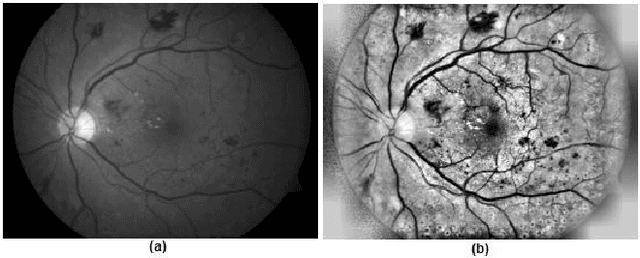

Abstract:Diabetic Retinopathy (DR) is among the worlds leading vision loss causes in diabetic patients. DR is a microvascular disease that affects the eye retina, which causes vessel blockage and therefore cuts the main source of nutrition for the retina tissues. Treatment for this visual disorder is most effective when it is detected in its earliest stages, as severe DR can result in irreversible blindness. Nonetheless, DR identification requires the expertise of Ophthalmologists which is often expensive and time-consuming. Therefore, automatic detection systems were introduced aiming to facilitate the identification process, making it available globally in a time and cost-efficient manner. However, due to the limited reliable datasets and medical records for this particular eye disease, the obtained predictions accuracies were relatively unsatisfying for eye specialists to rely on them as diagnostic systems. Thus, we explored an ensemble-based learning strategy, merging a substantial selection of well-known classification algorithms in one sophisticated diagnostic model. The proposed framework achieved the highest accuracy rates among all other common classification algorithms in the area. 4 subdatasets were generated to contain the top 5 and top 10 features of the Messidor dataset, selected by InfoGainEval. and WrapperSubsetEval., accuracies of 70.7% and 75.1% were achieved on the InfoGainEval. top 5 and original dataset respectively. The results imply the impressive performance of the subdataset, which significantly conduces to a less complex classification process